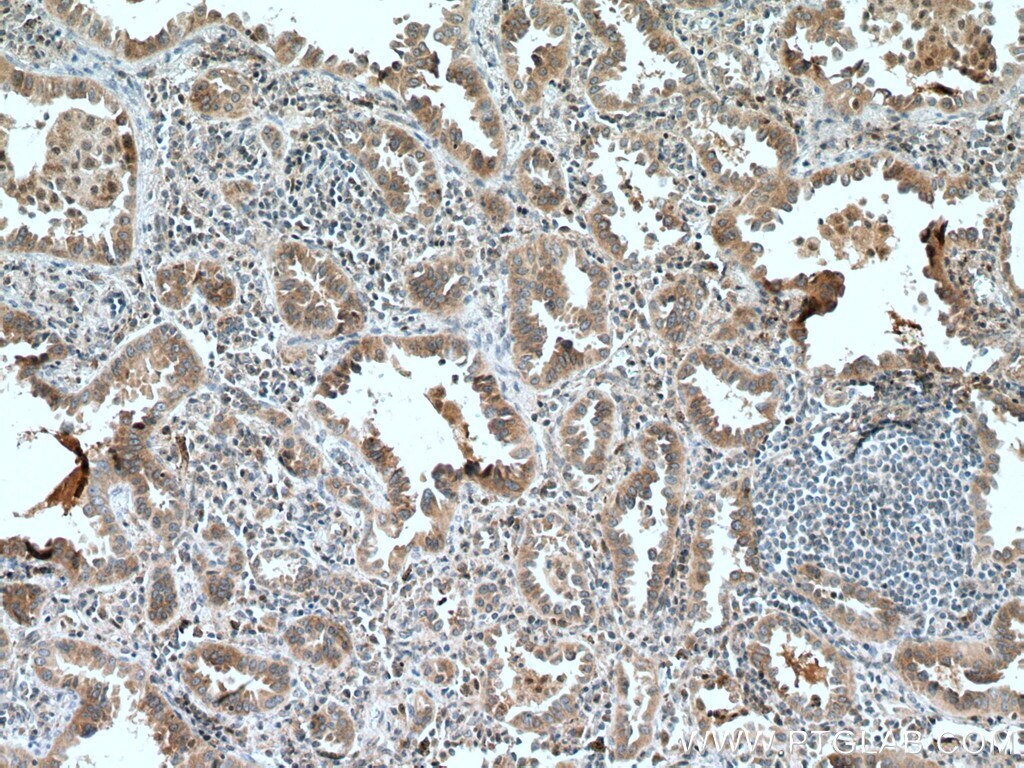

Supportive validation

- Submitted by

- Invitrogen Antibodies (provider)

- Main image

- Experimental details

- Immunohistochemistry of paraffin-embedded human lung cancer tissue slide using 10420-1-AP (SLC25A3 antibody) at dilution of 1:200 (under 40x lens) heat mediated antigen retrieved with Tris-EDTA buffer (pH 9).